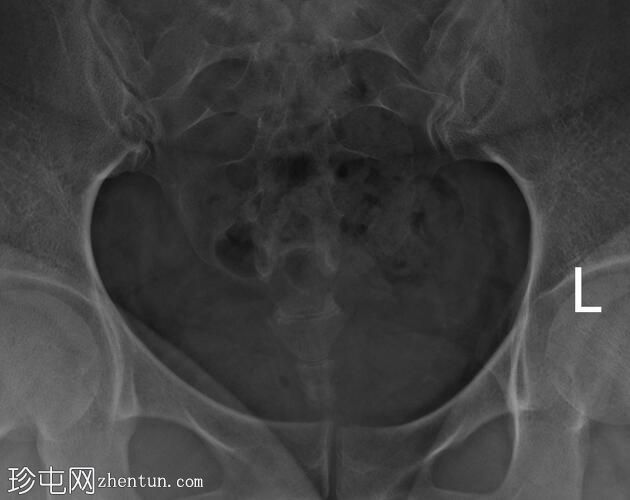

子宫体位于盆腔右侧旁中线,形态及轮廓正常。

宫颈管长度及黏膜表面正常,扩张正常。

右侧输卵管充盈,呈逐渐扩张,内有造影剂残留,无因输卵管积水导致的造影剂溢出。

左侧输卵管出现腹膜溢出。